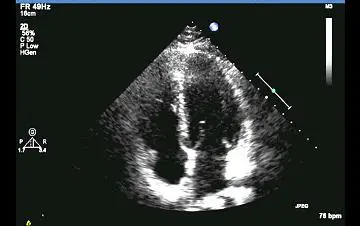

關於下圖心臟超音波的敘述,下列何者錯誤?

A此張超音波可辨認出左心房、左心室以及右心房、右心室

B此張心臟超音波為心尖四腔室圖

C此張超音波可診斷中度二尖瓣逆流

D此張超音波可看到二尖瓣與三尖瓣

本題探討2D B-mode transthoracic echocardiography(TTE)的apical four-chamber (A4C) 視圖特徵,以及單純灰階影像在診斷瓣膜返流上的限制。

• 心尖位於畫面頂端中央,室間中隔(IVS)呈近乎垂直於扇形掃描線,符合apical取向

• 左側近場結構為左心室(LV)與左心房(LA),右側近場為右心室(RV)與右心房(RA)

• 左側瓣膜為Mitral Valve(MV),右側瓣膜為Tricuspid Valve(TV),瓣膜開合清晰可辨

此為典型A4C視圖,旨在同時呈現四腔室與兩側房室瓣葉運動。